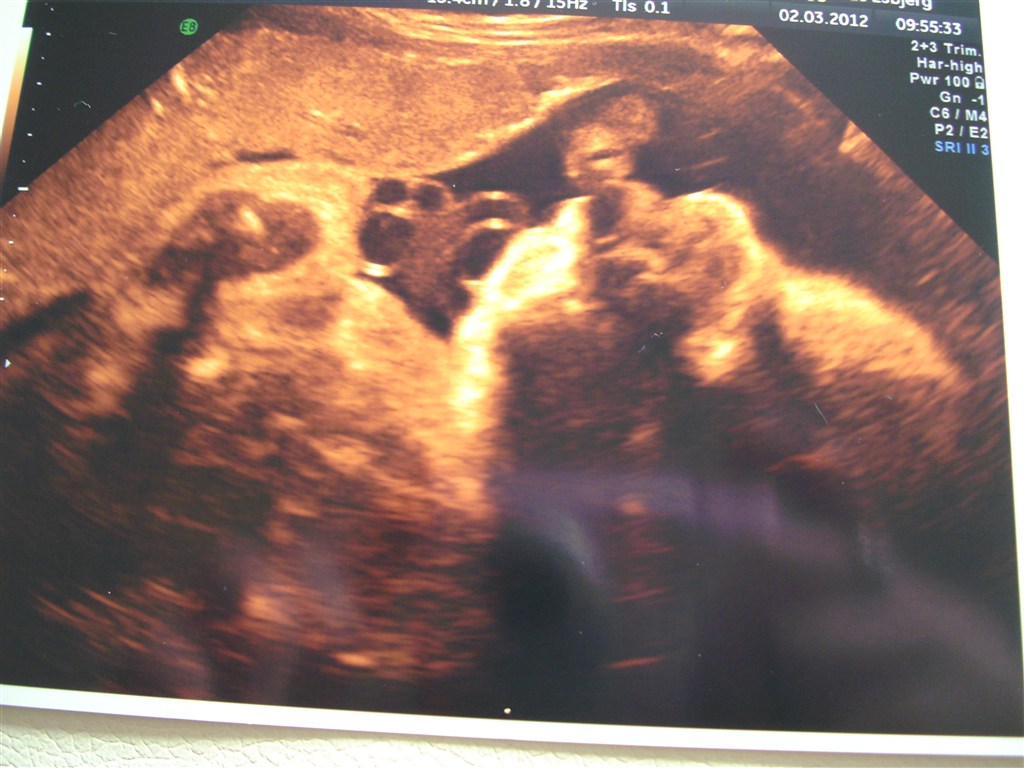

ja som overskrifter siger så kommer der nogle billeder fra skanningen idag af

har været til vægt skanning og de skød ham til ca. 2500 g så det er jo super!

Vedhæftede fotos (klik for at se i fuld størrelse)

Takker! & håber jeg også hvis han vælger han komme nu her, selvom han godt lige må vente en ugestid endnu & takker, syntes også det er nogle vidunderlige billeder jeg har fået af ham!